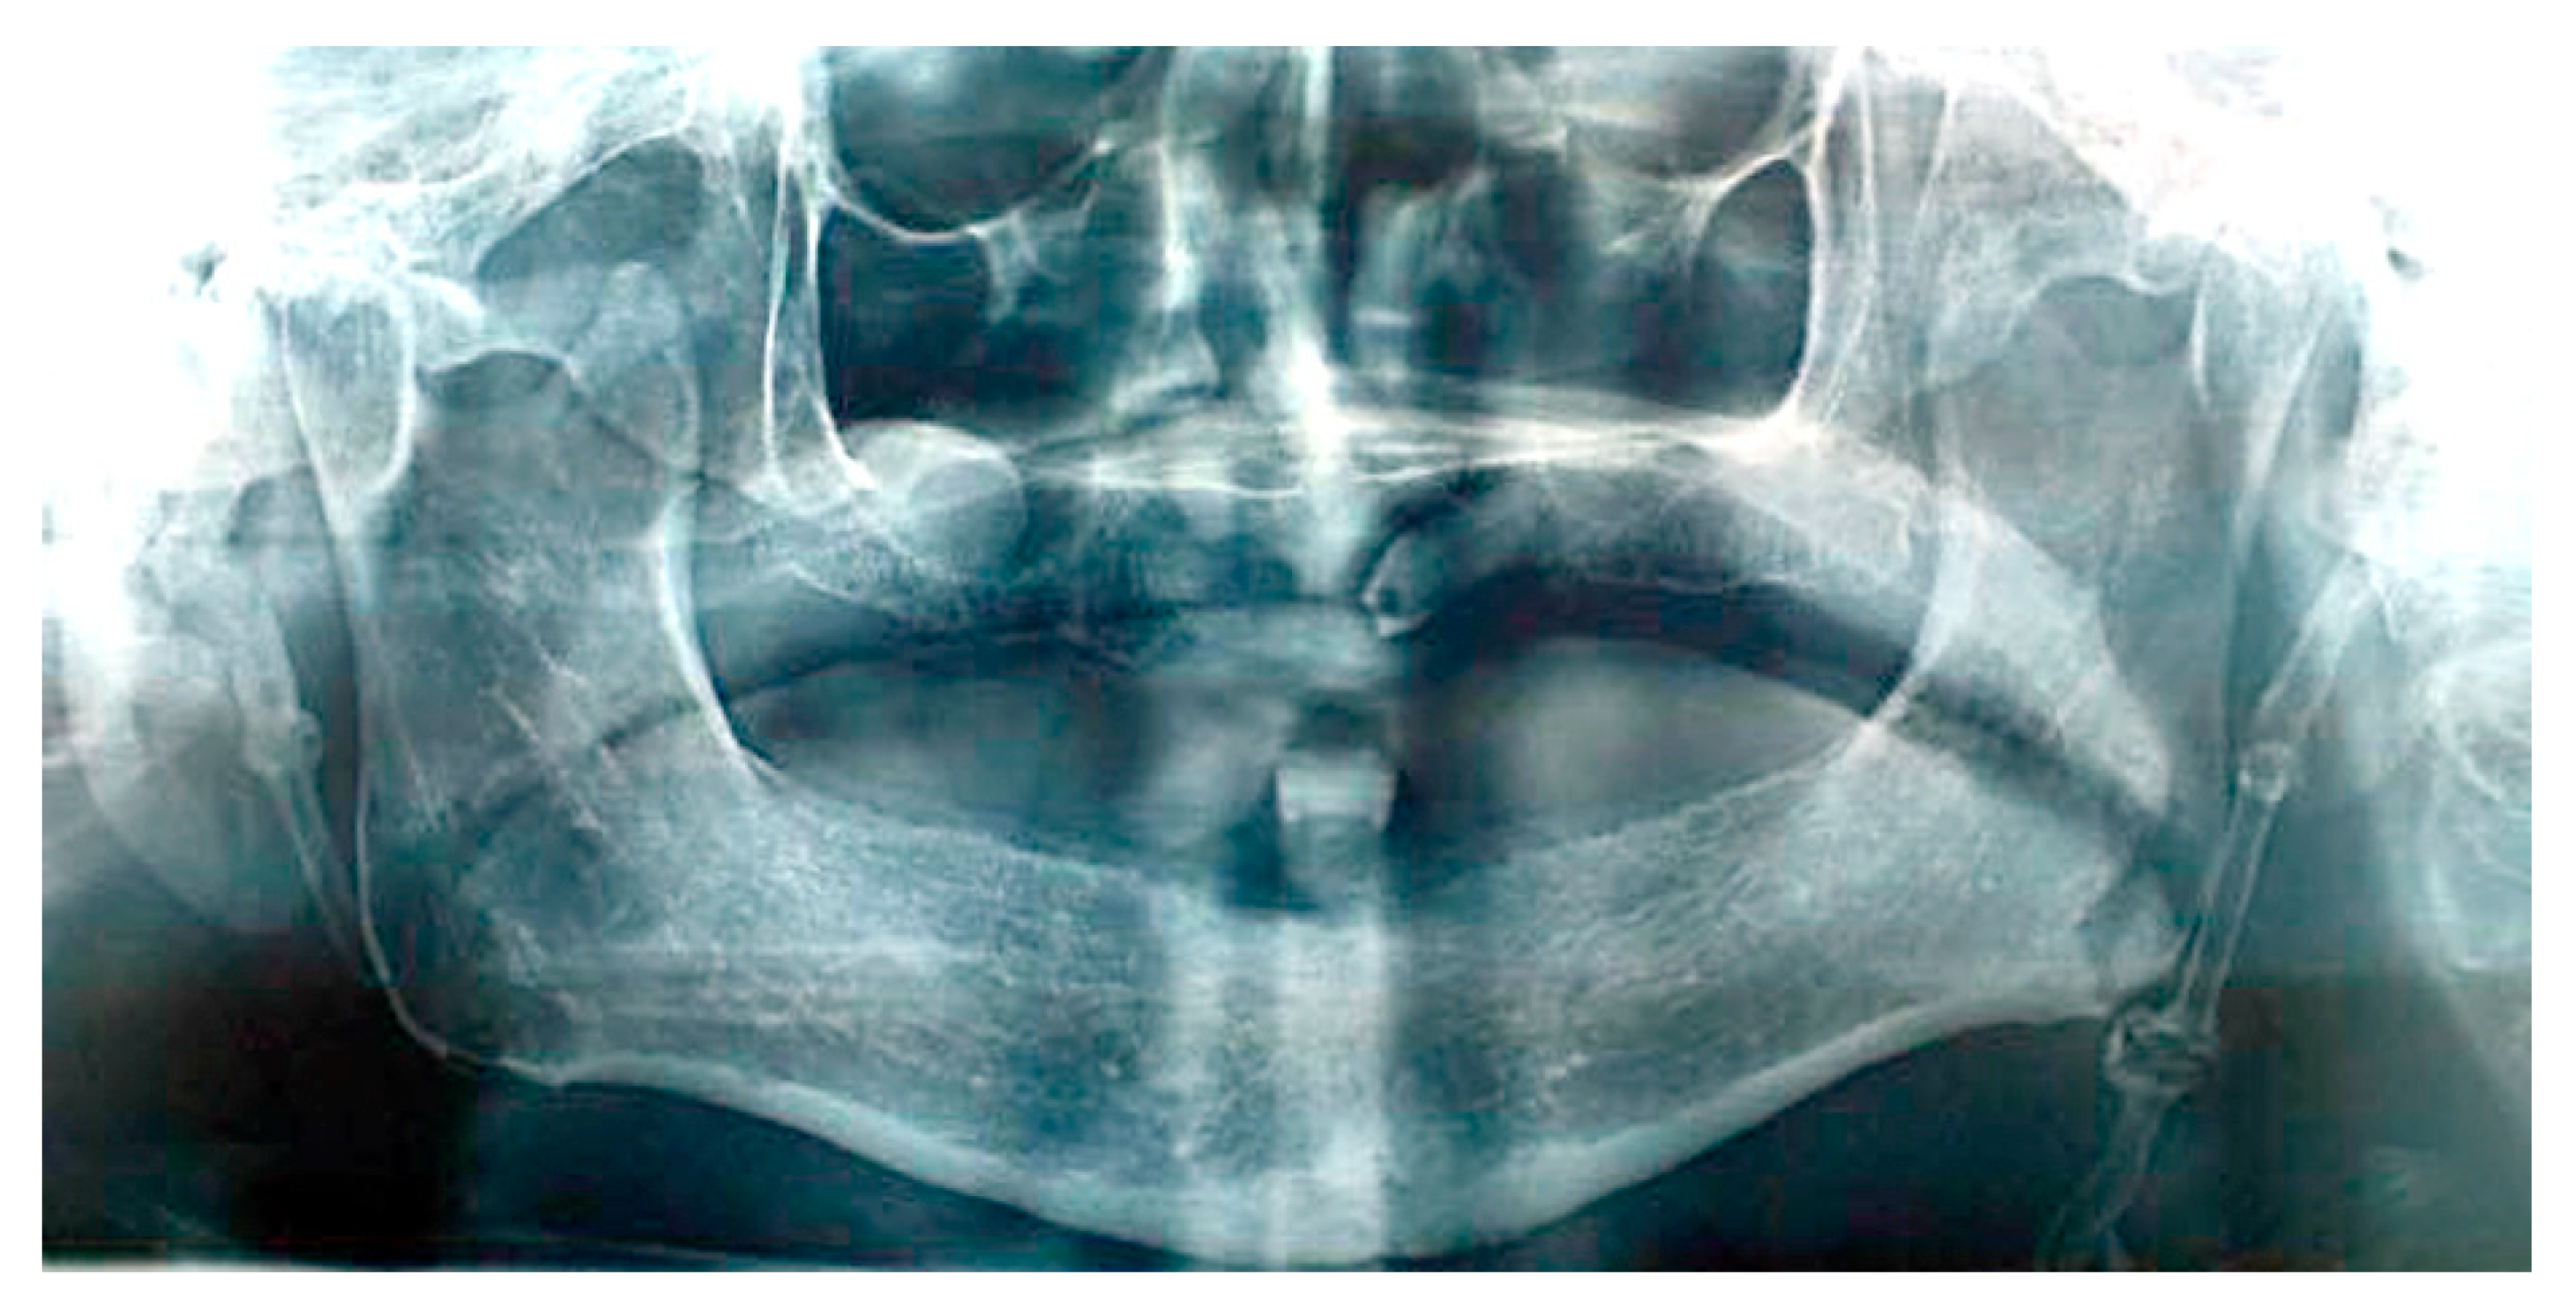

The patient’s orofacial region was thoroughly examined with no clinical findings indicating the cause of her pain episodes. However, oropharyngeal examination showed severe tenderness and pain on palpation in the right tonsillar region, with motion pain occurrence during head horizontal rotation. Panoramic X-ray acquisition showed pathological elongation of the right styloid process, like a “thorn” with a length of 49 mm by manual measurement with a ruler (Figure 1).

Figure 1. Cropped panoramic image showing pathologically elongated styloid process ending at the inner side of angle of mandible. The length of styloid process is 46 mm (conventional manual measurement with straight ruler).

In the panoramic view, when the styloid process is elongated, it attains over one third of the mandibular ramus length [18], which is presented on the panoramic image in patient #1. Taking all the obtained clinical facts into account (clinical symptoms and panoramic image) in the described case, diagnosis with proper subsequent surgical treatment of true Eagle’s syndrome was made in patient #1.